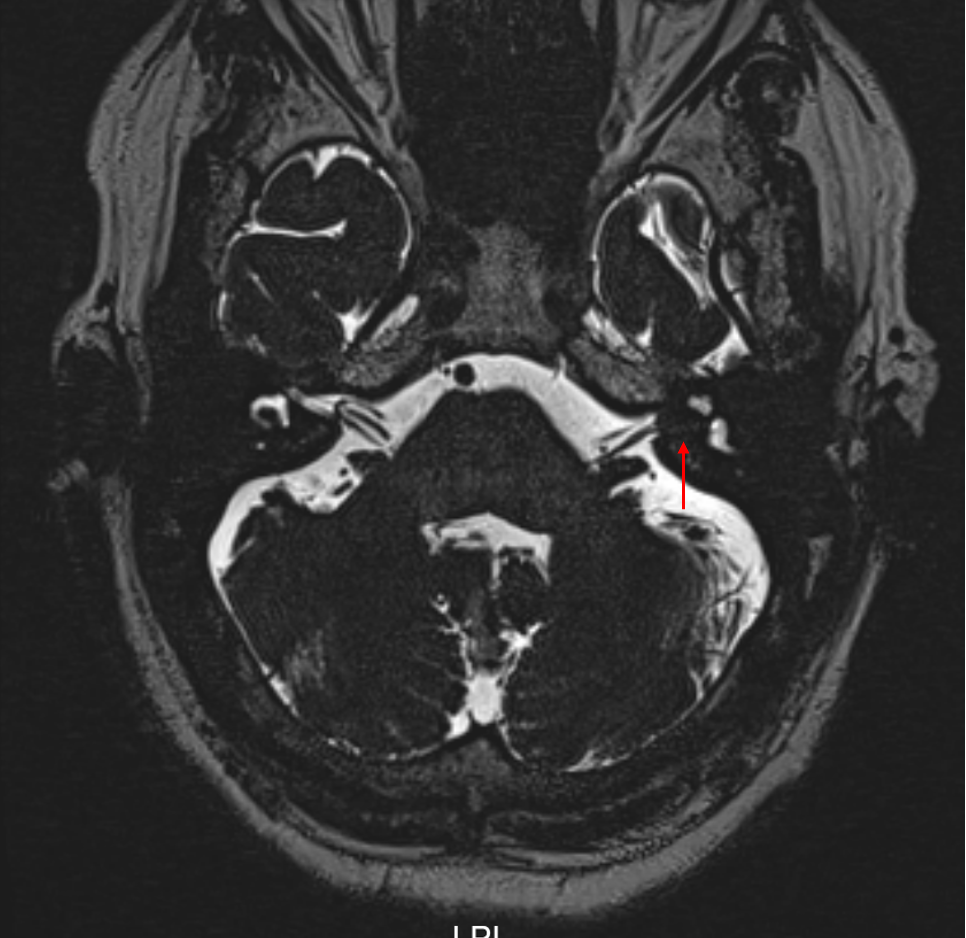

内听道磁共振提示:左侧内听道内占位

红色箭头所指位置,可见内听道内的脑脊液(白色)被椭圆形的占位性病变(黑色)排开